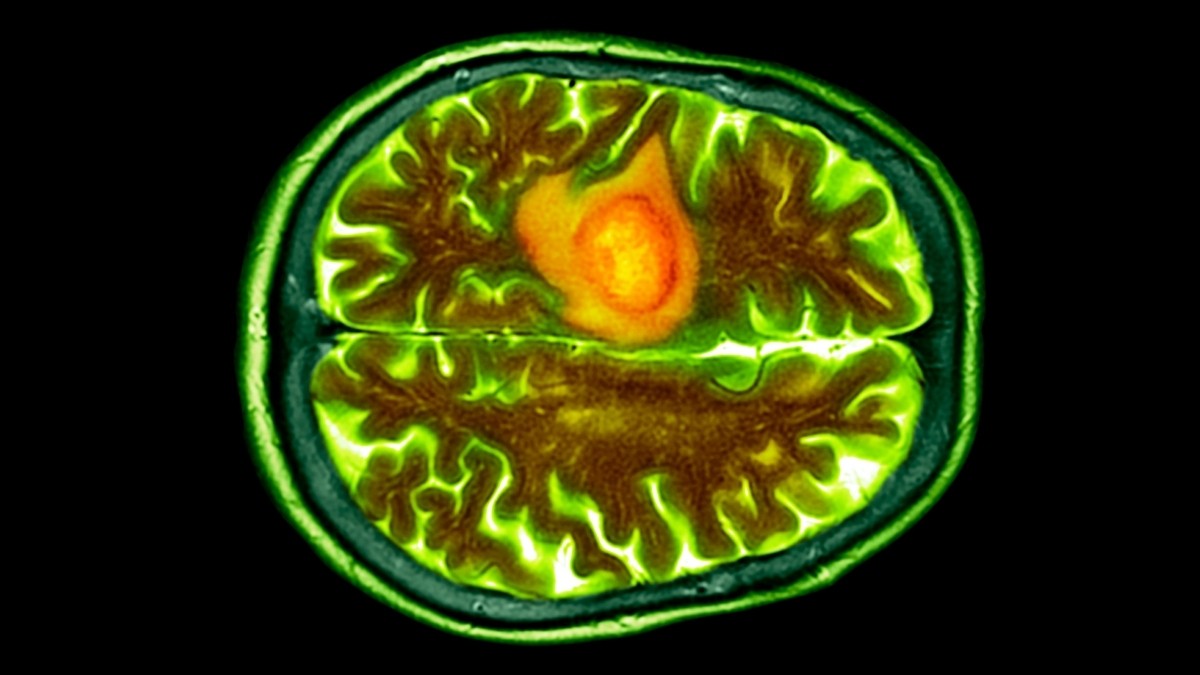

Forscher haben einen neuartigen Ansatz zur Behandlung von Glioblastomen, einer der aggressivsten und tödlichsten Formen von Hirntumoren, entwickelt: Nasentropfen, die Medikamente direkt an das Zentralnervensystem abgeben. Frühe Tests an Mäusen belegen die Fähigkeit der Therapie, Tumore sicher zu erreichen und eine Immunantwort auszulösen, was einen möglichen Durchbruch in einem Bereich darstellt, in dem die Behandlungsmöglichkeiten stark begrenzt sind.

Glioblastomtumoren sind bekanntermaßen schwer zu behandeln. Sie wachsen schnell, entziehen sich der körpereigenen Immunabwehr und bilden sich in Bereichen des Gehirns, die mit herkömmlichen Therapien schwer zugänglich sind. Der Krebs verursacht Schwellungen, komprimiert gesundes Gehirngewebe und stört den lebenswichtigen Blutfluss, was zu verheerenden neurologischen Beeinträchtigungen führt. Nur 6,9 % der Patienten überleben länger als fünf Jahre nach der Diagnose, was den dringenden Bedarf an neuen Behandlungsstrategien unterstreicht.